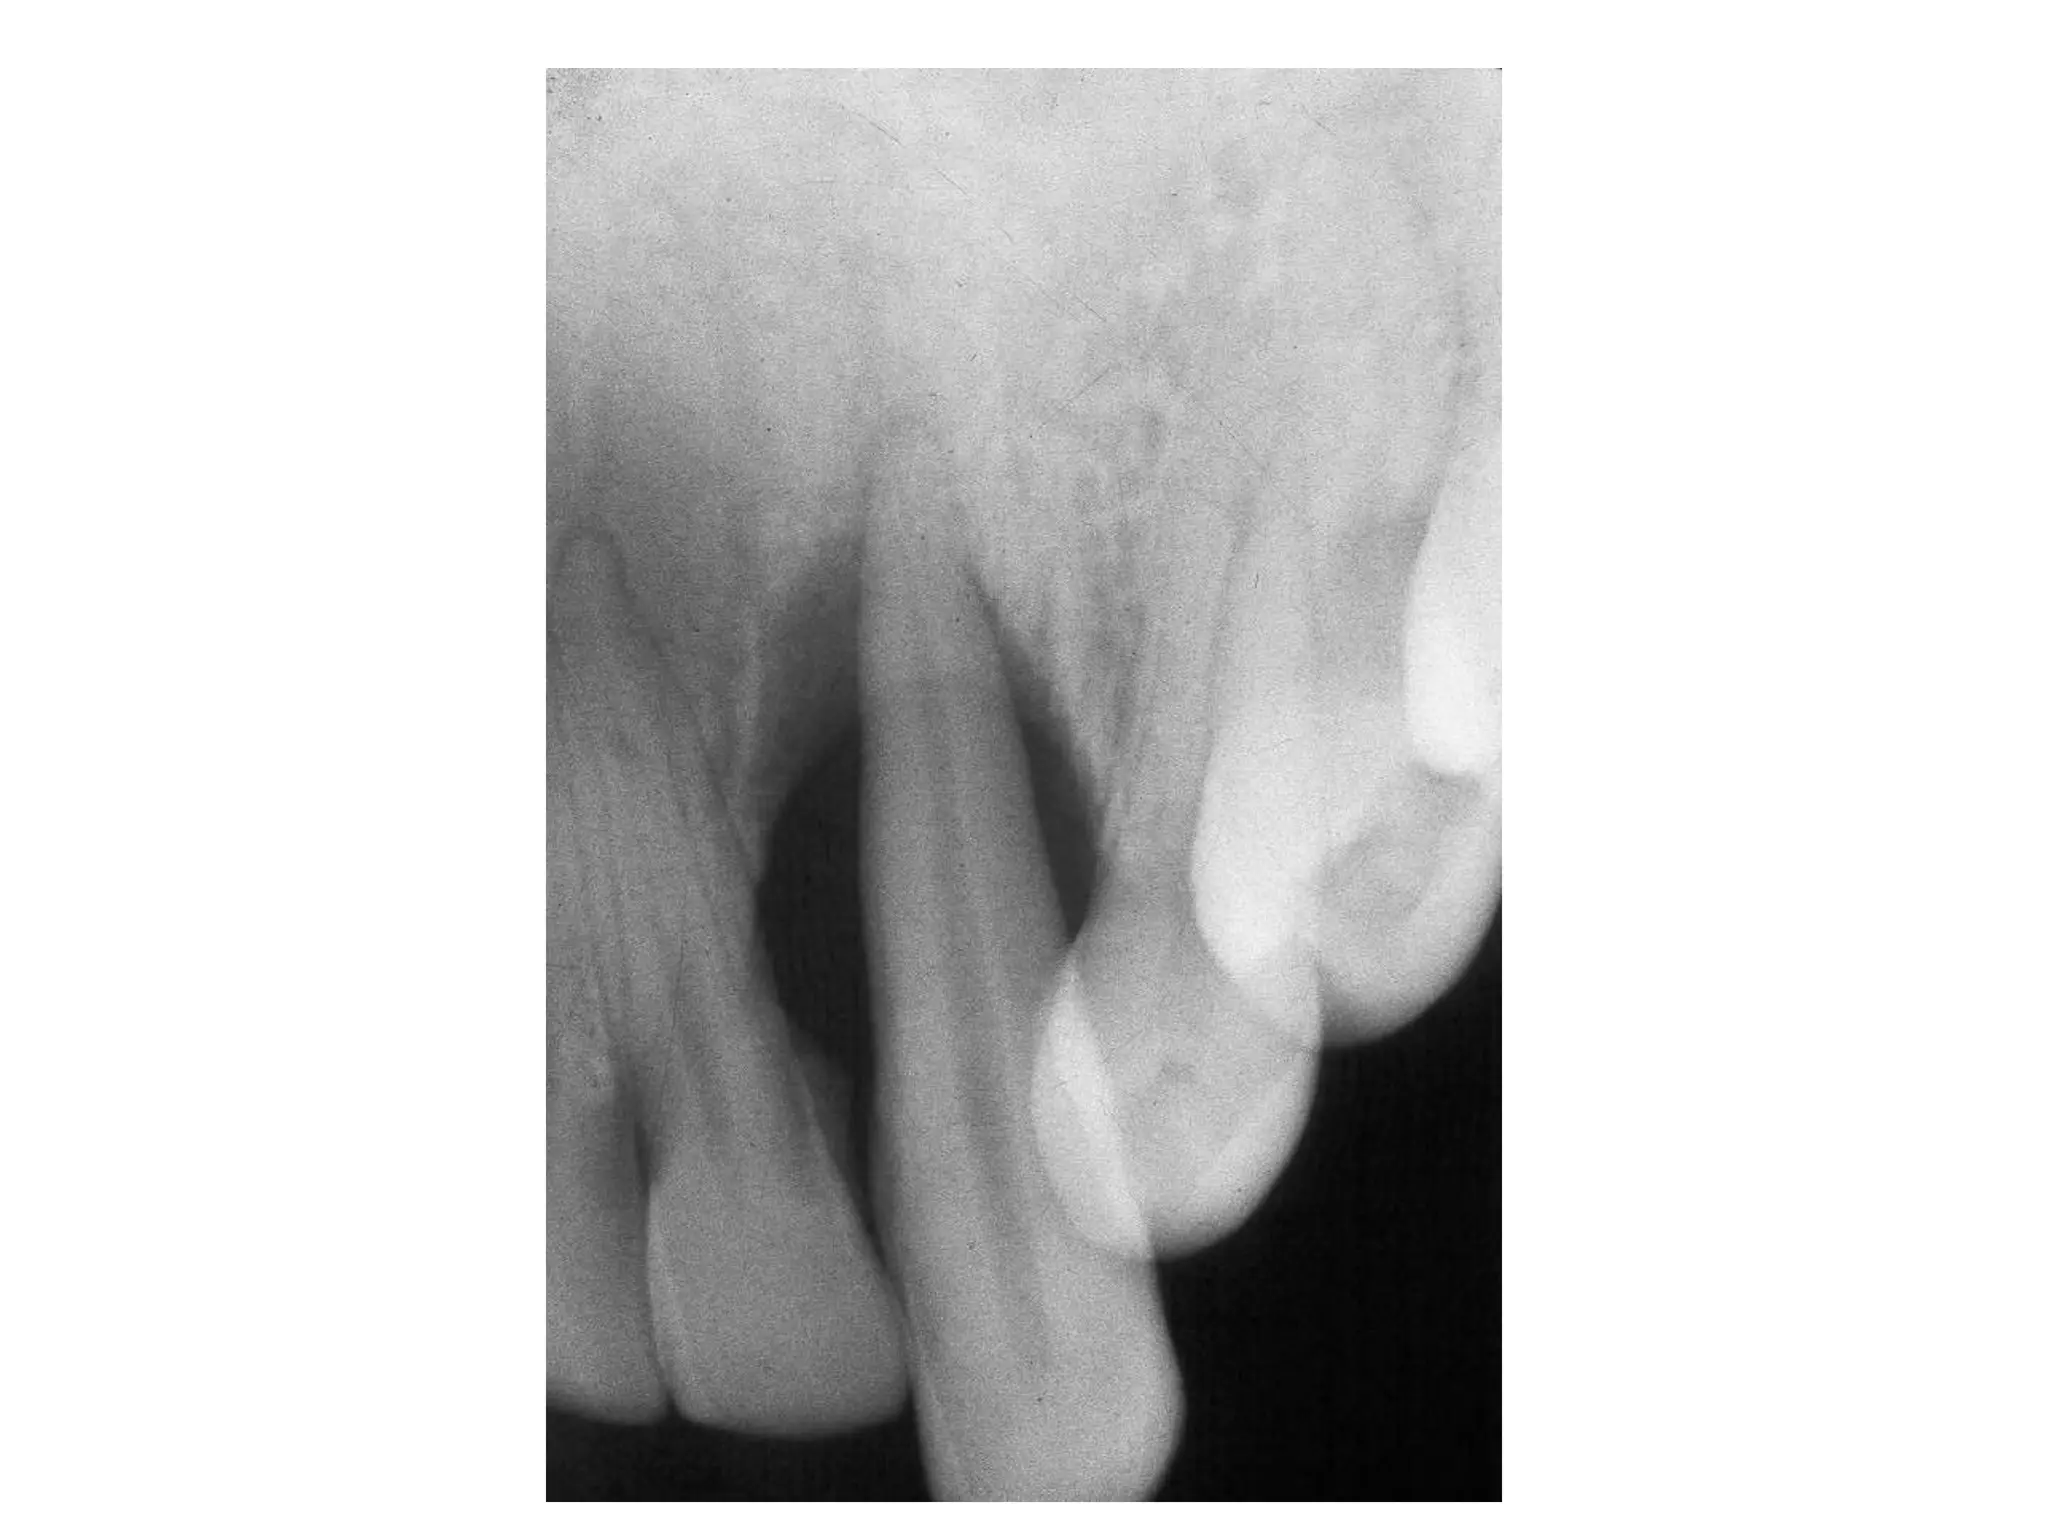

Moderate Adult Periodontitis

Horizontal bone loss or vertical

osseous defects

Total extent of bone loss not evident

May have slight mobility

(red arrows point to calculus)